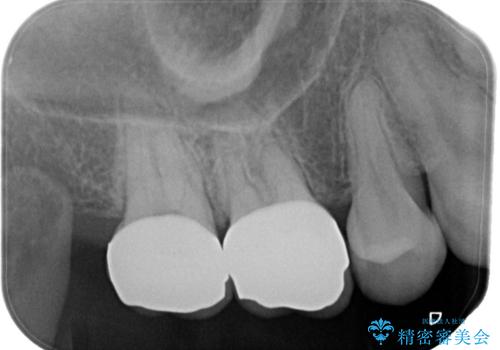

【オールセラミッククラウン】虫歯の治療

- 奥歯がかけたことを主訴に来院されました。

オールセラミッククラウンにて修復治療を行っております。

歯の破折強度を高めるためにクラウンによる修復を希望され、治療を行っております。